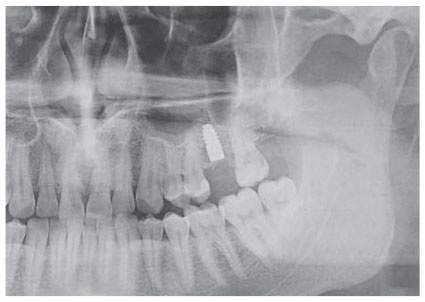

В каком-то смысле формирование нового образа жизни напоминает процесс восстановления после операции. Например, имплантации зуба.

Иллюстрация к книге — Путь джедая [i_040.jpg]

Рис. 40. Рентгеновский снимок имплантата

Если вам нужно поставить себе имплантат, будьте готовы, что это не произойдет слишком быстро, даже если вы не будете прокрастинировать [52] эту задачу. Технологически процесс устроен так, что нужны длительные временные отрезки, на протяжении которых организм адаптируется к изменениям. В моем случае сначала удалили зуб: 15 минут работы и три месяца ожидания, пока заживет. Потом посмотрели, как идет процесс заживления, и решили подождать еще немного (пять минут работы и три месяца ожидания). Потом вкрутили имплантат (на снимке) и добавили костной ткани: 20 минут работы и три месяца ожидания, пока кость примет костную ткань и имплантат.